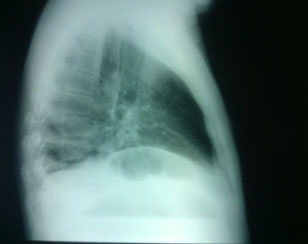

La tele de tórax mostró un hemidiafragma derecho elevado con nivel hidroaéreo, por lo que hubo sospecha de absceso pulmonar (figuras 3 y 4). Por lo tanto, se llevó a cabo una TAC de tórax en la que se observó una imagen redondeada con doble nivel hidroaéreo de aspecto tabicado, condensación basal derecha y derrame pleural, sin adenomegalias. El reporte de radiología fue de empiema derecho (figuras 5 y 6).